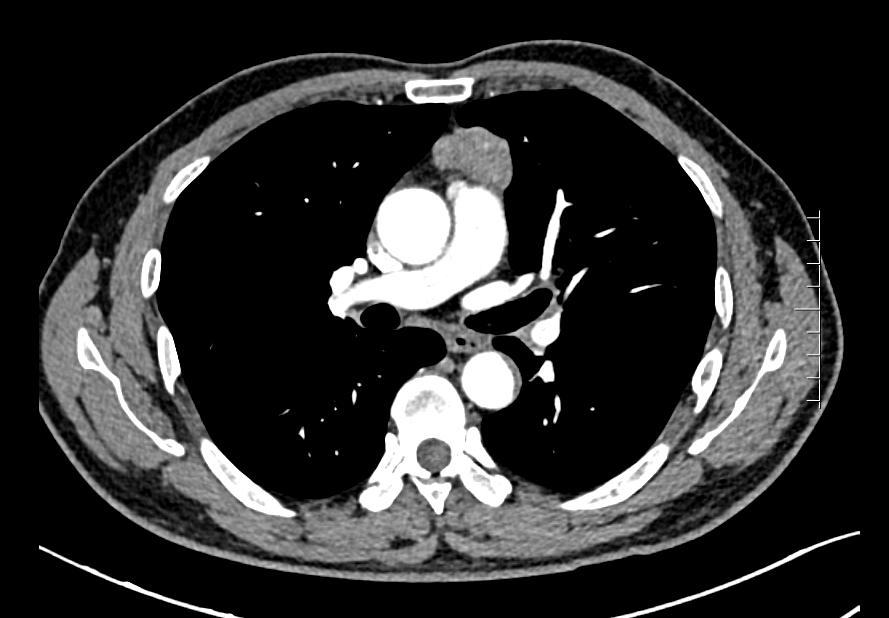

该名患者因肌无力症状在体检时发现前纵隔占位,CT提示前纵隔结节影,长径约4cm,考虑胸腺瘤。胸外科结合患者病情、既往史,并与患者及家属充分沟通后,决定为患者行“经皮天平拉钩剑突下单孔VATS前纵隔占位切除术”。